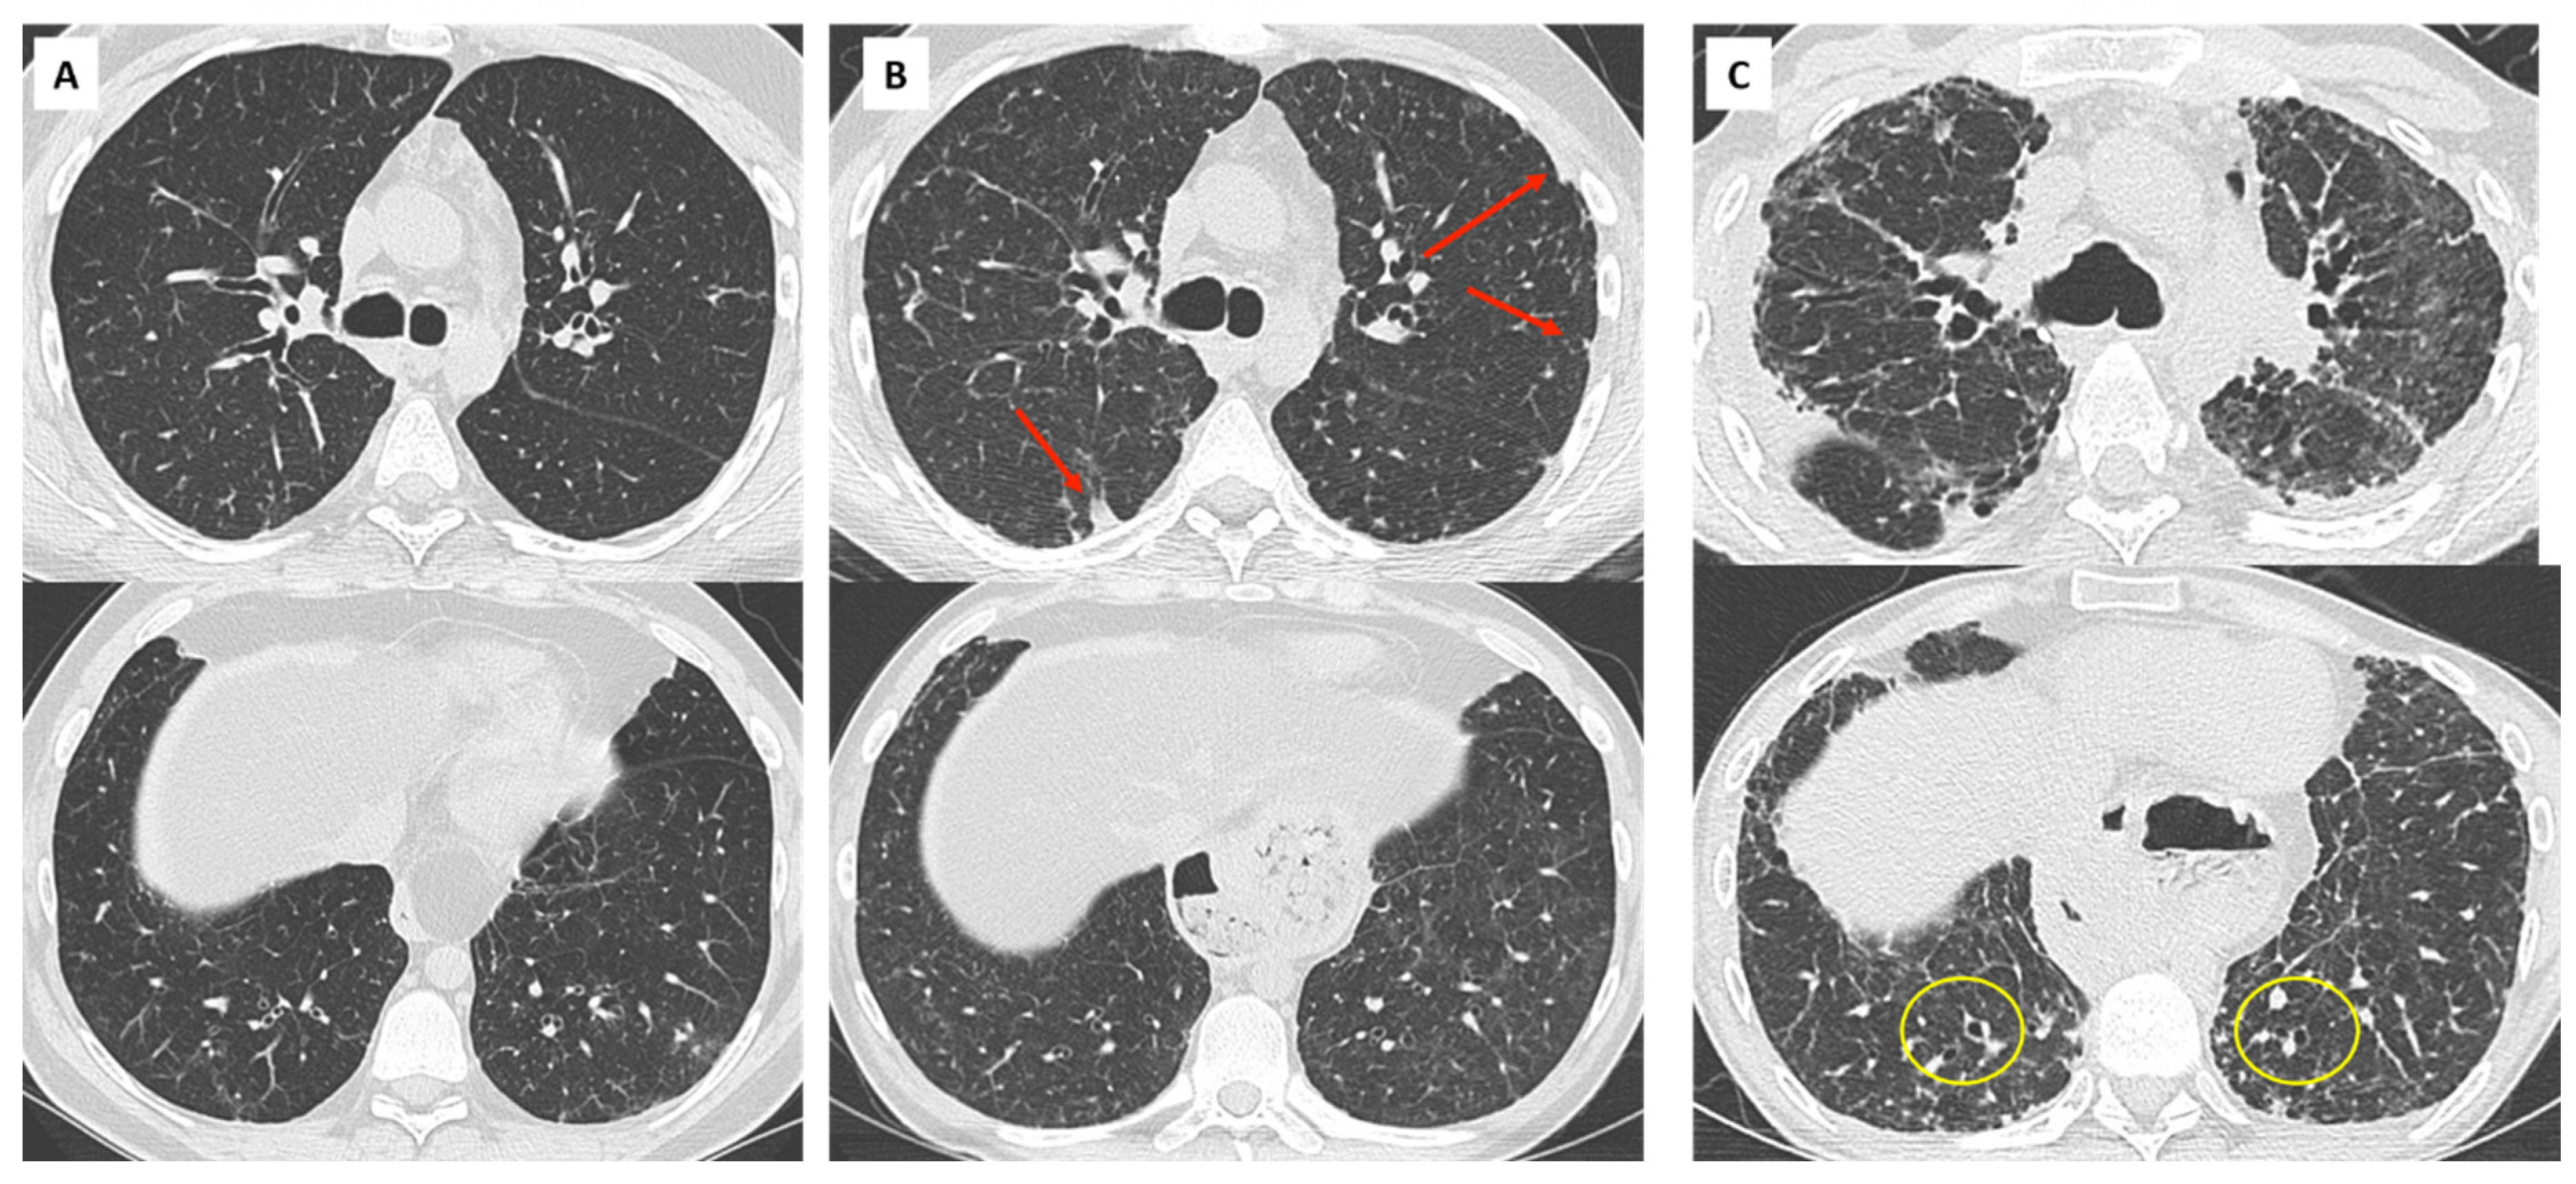

6. Overlap BOS/RAS: Mixed-Phenotype CLAD